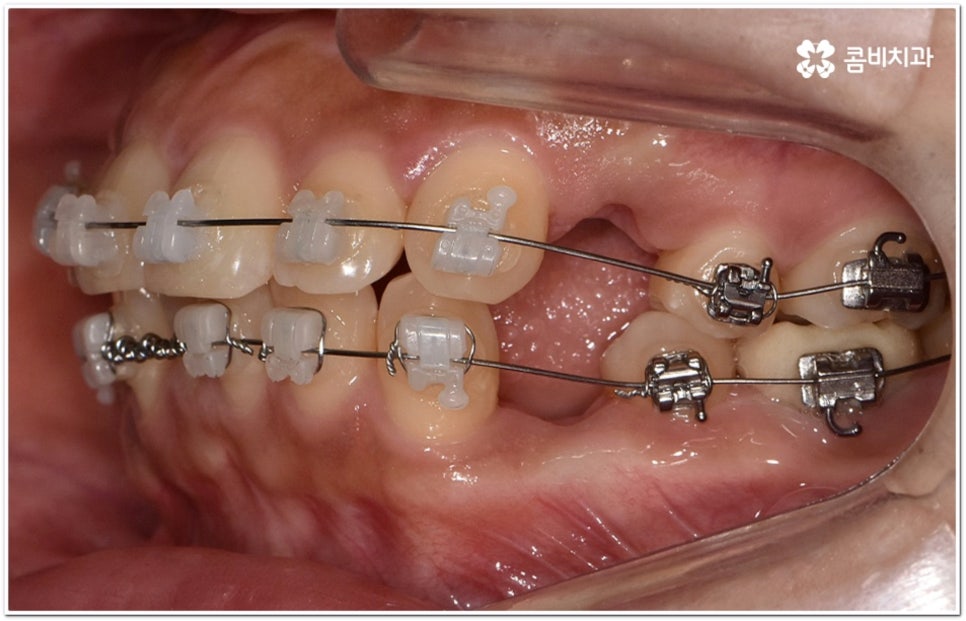

환자마다 치열, 교합, 치아가 튀어나온 각도, 잇몸이 드러나는 정도, 상악과 하악의 구조 및 관계 등 턱관절 관련 부분 상황이 모두 다르기 때문에 3D CT 같은 정밀 검진 기계를 통해 이를 꼼꼼하게 살펴보고 각각에 맞는 계획을 세밀하게 세워 교정 치료를 진행해 줄 필요가 있어요. 이때 환자분들의 상황에 따라 양악수술과 같은 외과적인 방법을 병행해야 하는 케이스도 있을 수 있기 때문에 돌출입을 가지고 계신 분들 중에서 수술에 부담을 느끼고 지레 치료를 포기하신 분들도 있을 수 있는데 정도가 많이 심각하지 않고 구조적인 원인이 크지 않다면 대부분의 케이스는 치아교정 만으로도 충분히 개선이 가능하니 먼저 돌출입교정치과 에 들러서 정밀 검사를 진행한 후 치료 방향에 대해 의료진과 논의해 보시면 좋을 거예요.

말씀드렸던 것처럼 돌출입의 원인이 치아 만의 문제, 즉 각도가 살짝 앞으로 뻐드러진 데 있고 상태가 그다지 심한 것 같지 않다면 보다 빠르고 간편한 수복이 가능할 수 있어요. 튀어나온 부분을 집어넣기 위해서는 발치가 필수적이지 않을까 생각하실 수 있는데 후방으로 이동시켜 줄 공간이 충분하다면 치간 삭제, 악궁 확장, 어금니 후방 이동 등 다른 방법을 이용하여 비발치 치료 과정을 진행할 수 있으므로 너무 걱정하지 않으셔도 될 거예요. 오히려 환자분들의 다양한 상황을 고려하지 않고 무리하게 발치 교정을 진행하게 되면 옥니나 합죽이와 같은 부작용이 일어날 수도 있기 때문에 원인을 정확하게 파악하고 적절한 치료를 할 수 있도록 임상 경험이 풍부하고 뛰어난 노하우를 가지고 있는 숙련된 의료진에게 교정 치료를 맡기시는 것이 굉장히 중요하다고 할 수 있습니다.